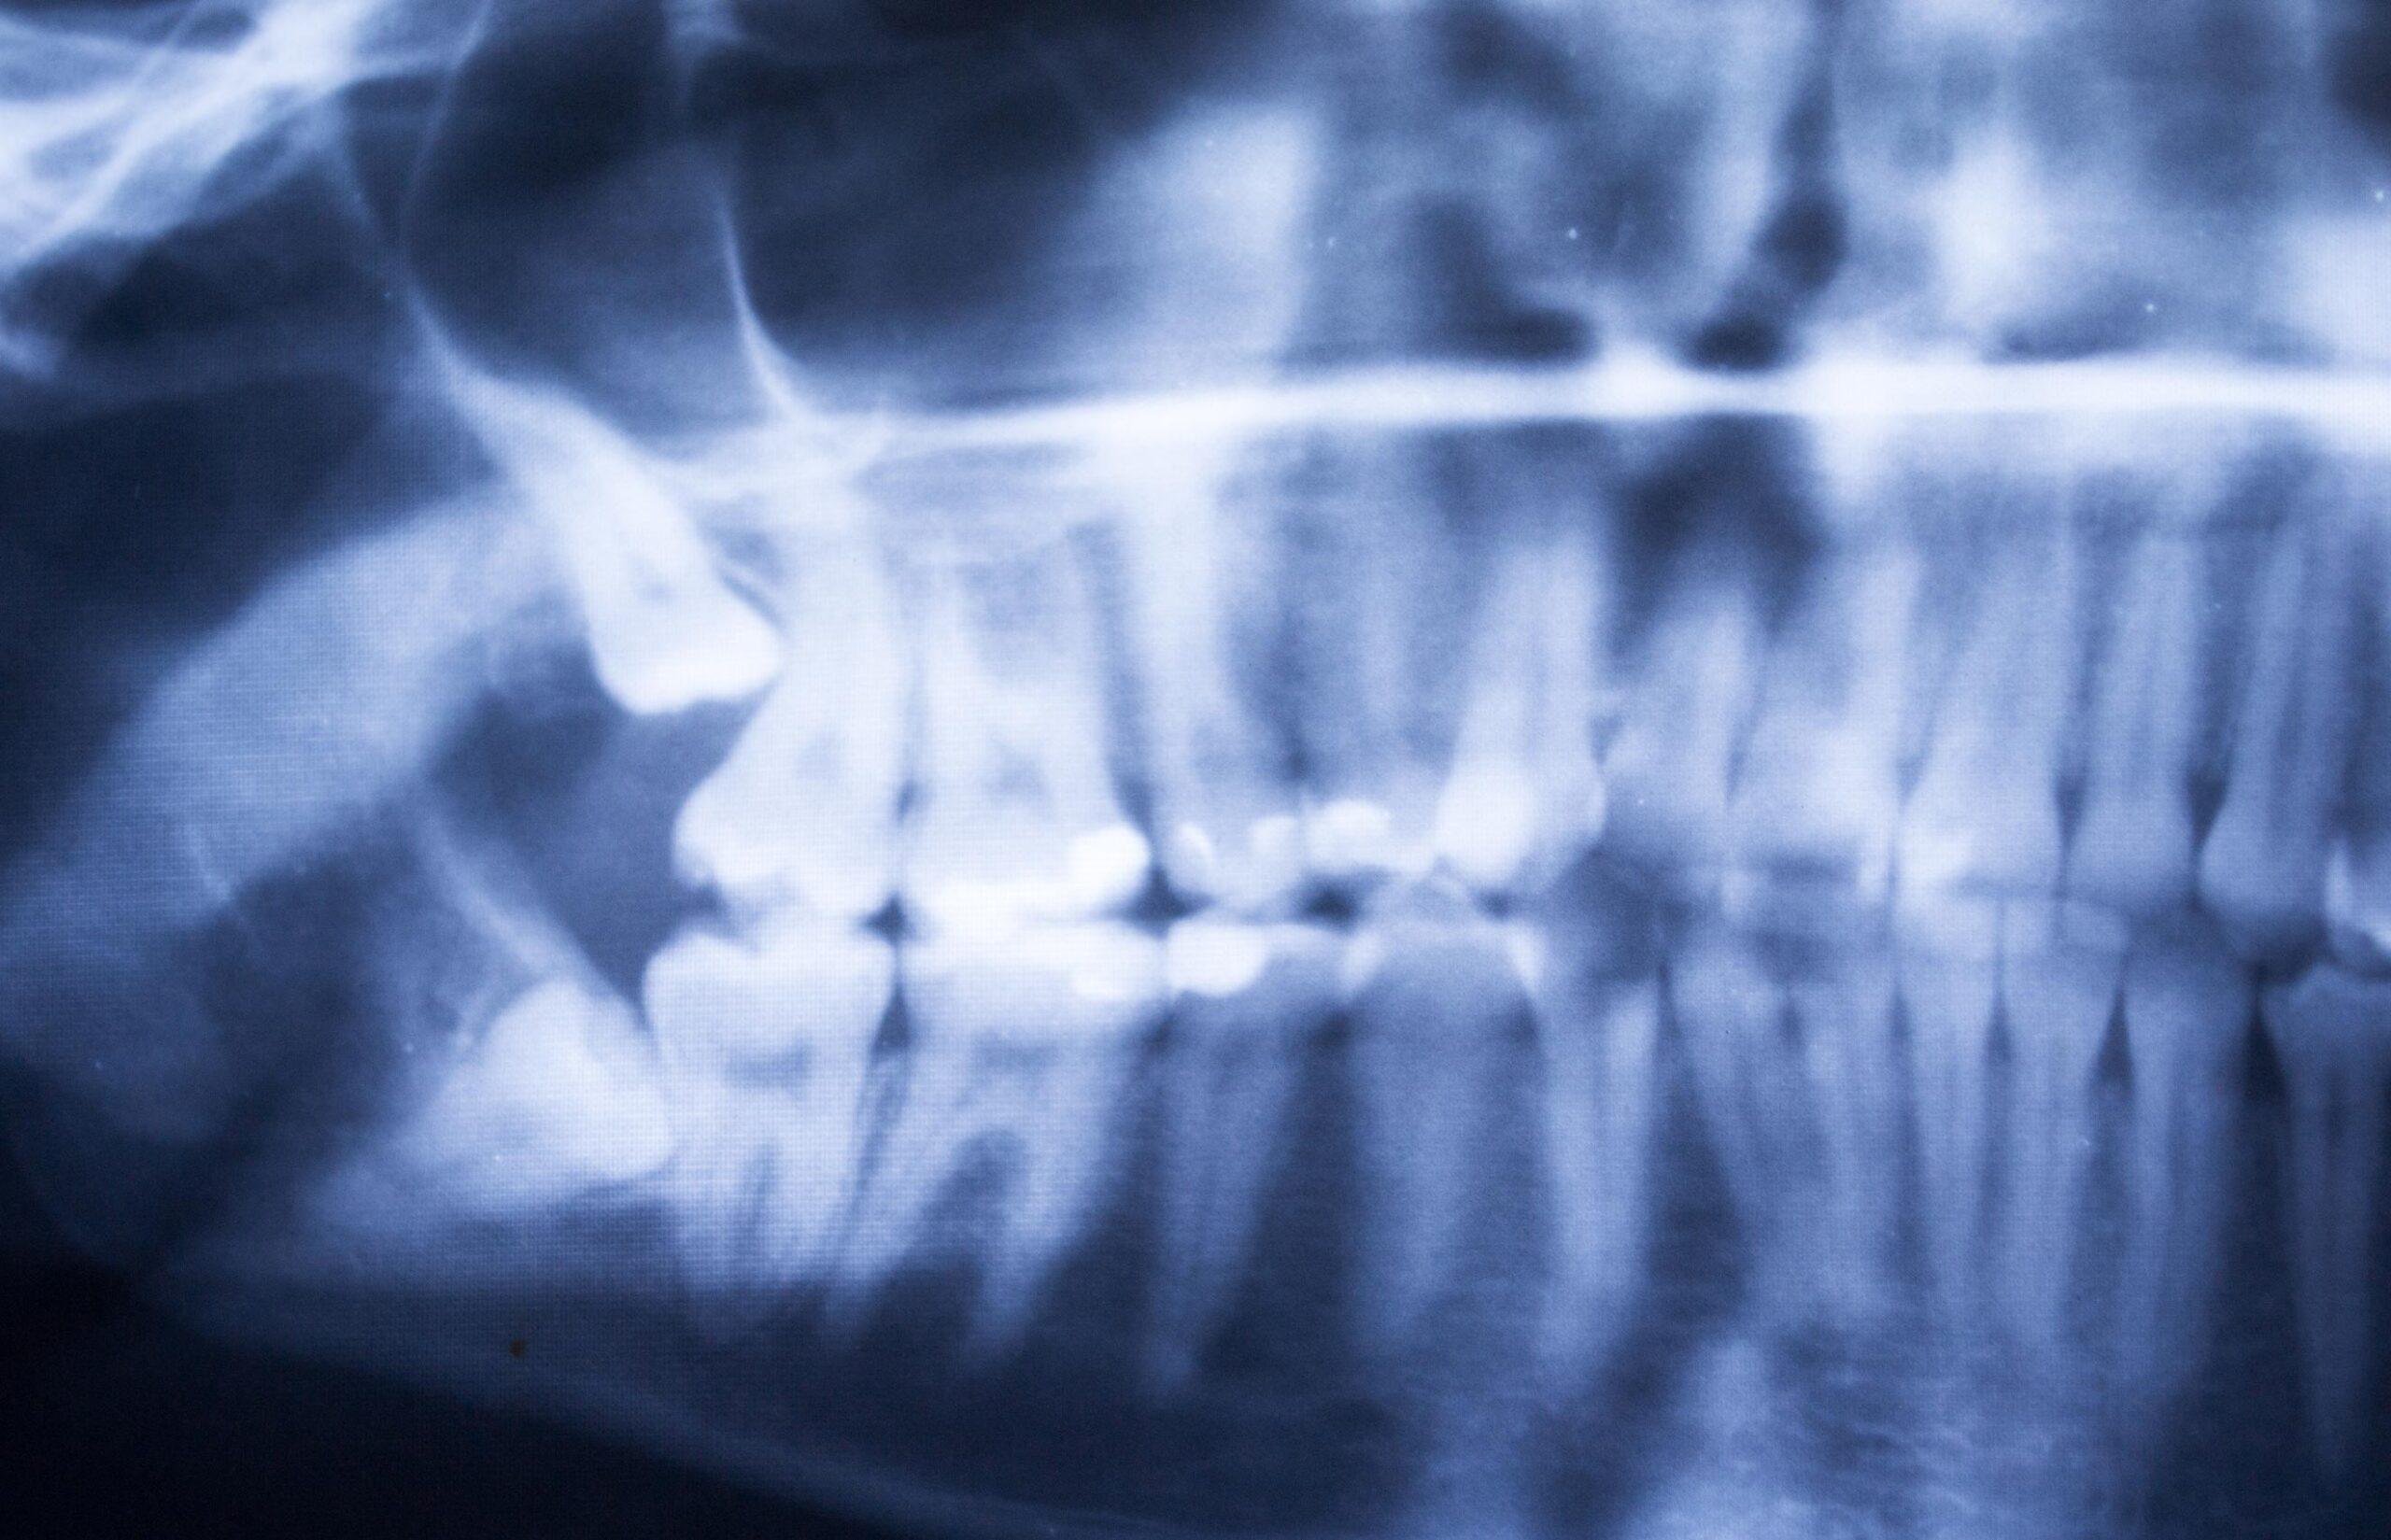

What to Expect During a Wisdom Tooth Evaluation

Before recommending removal, our dental team completes a thorough assessment to understand how your wisdom teeth are developing and whether intervention is necessary. Findings and treatment options are reviewed clearly so you can make informed decisions about your care.